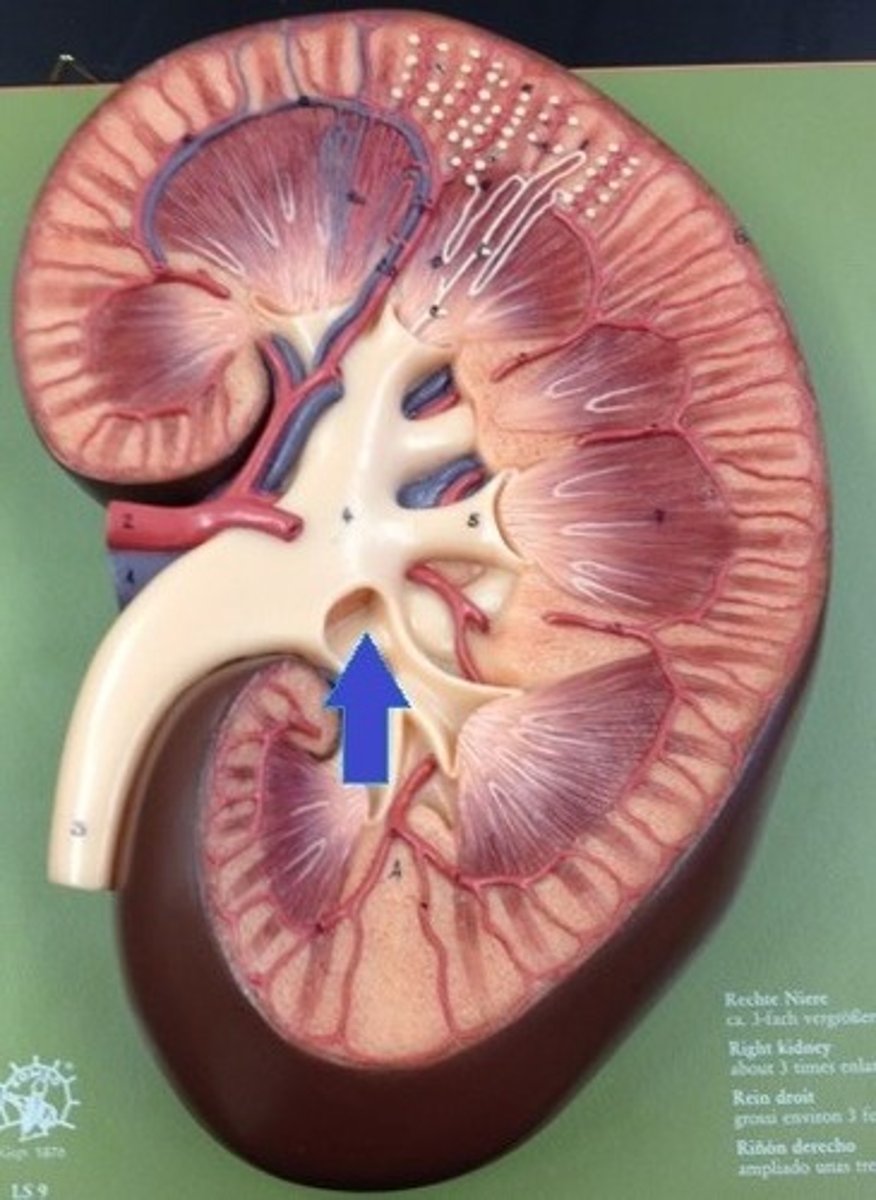

renal pyramids

striated triangular-shaped areas of tissue in the medulla of the kidney

renal papillae

medullary area of the renal pyramids where collecting ducts empty urine into the minor calyces

renal columns

extensions of cortex in between pyramids

minor calyx

cup that nestles the papilla of each pyramid; collects its urine

major calyx

urine passageway

renal pelvis

central collecting region in the kidney

renal artery

Supplies blood to the kidneys.

segmental artery

move blood from renal artery to interlobar artery

interlobar artery

move oxygenated blood from segmental artery to arcuate artery

arcuate artery

cortical radiate artery

take blood to afferent arteriole that enters glomerulus